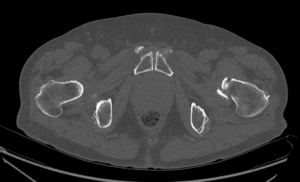

TC simple axial